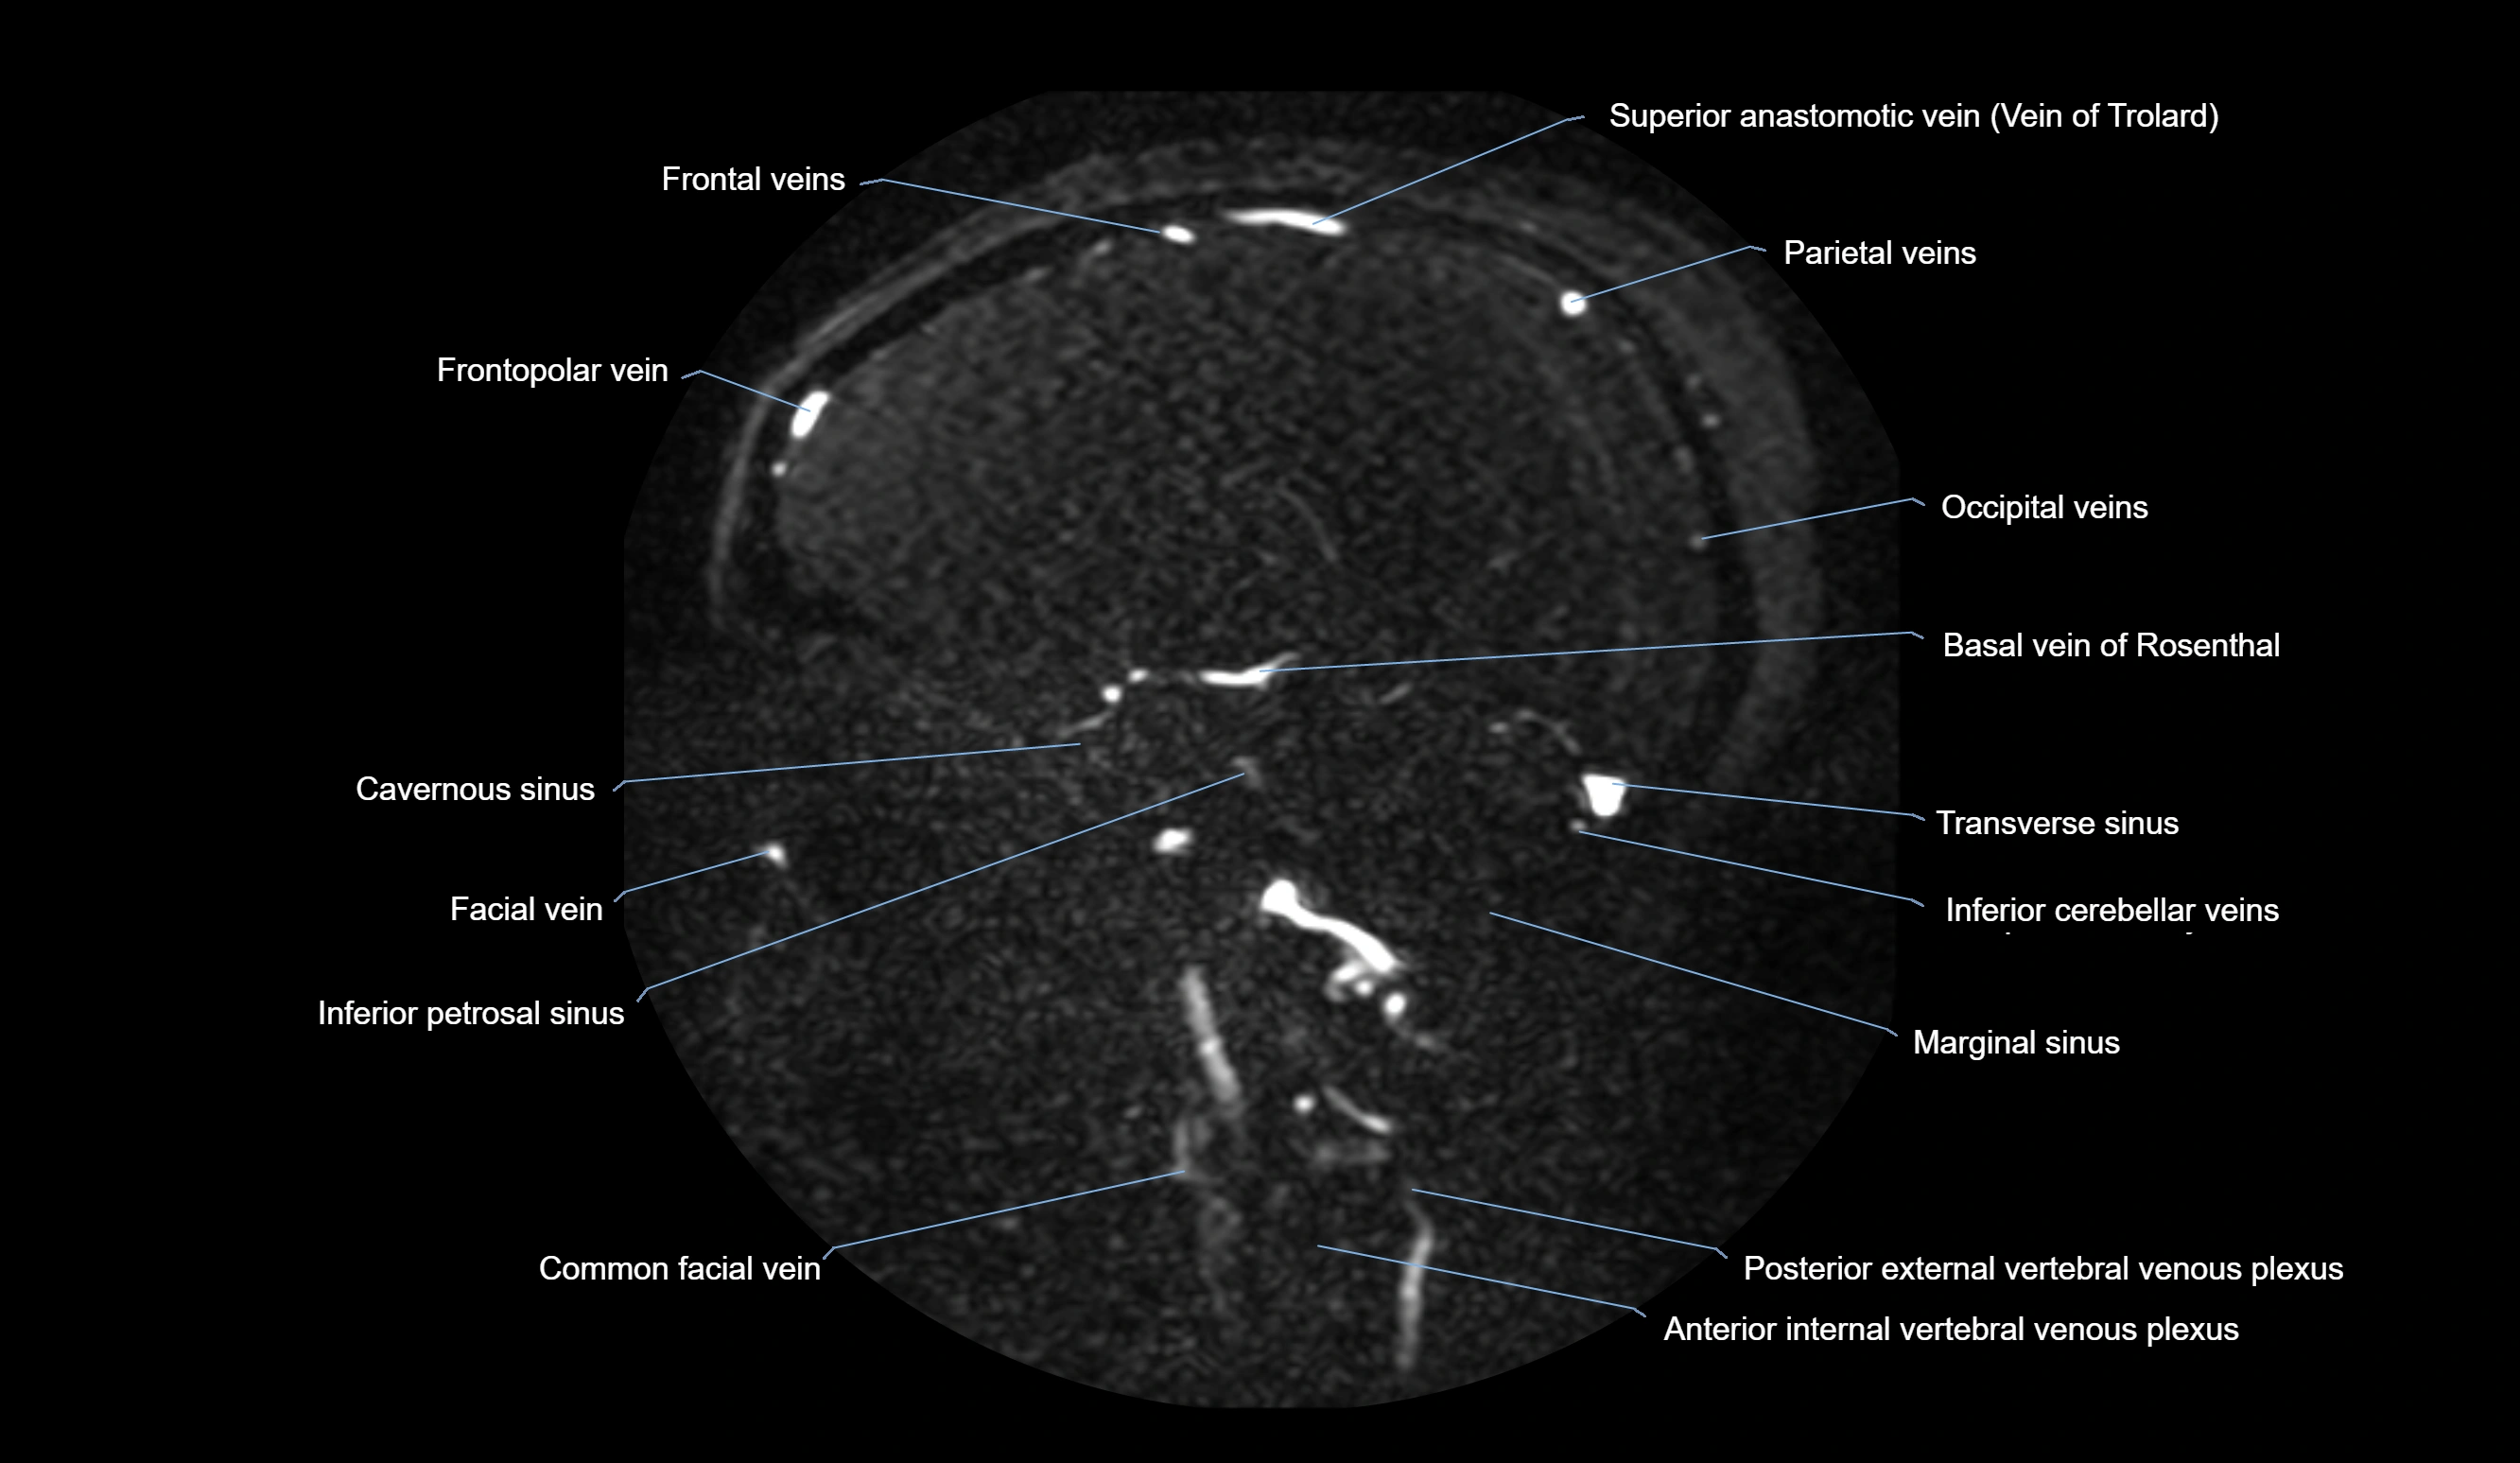

CT Venography (CTV):

• Clearly visualizes the angular vein as a contrast-filled venous channel

• Demonstrates its communication with the facial vein, superior ophthalmic vein, and cavernous sinus

• Essential for detecting facial vein thrombosis, orbital venous involvement, and cavernous sinus pathology